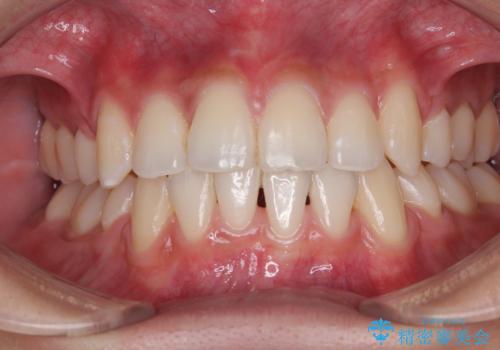

[ マウスピース矯正] 前歯のがたつき 出っ歯に見える歯をきれいに

担当医 大元洋佑

![[ マウスピース矯正] 前歯のがたつき 出っ歯に見える歯をきれいに の症例 治療前](https://seimitsushinbi.jp/wp/wp-content/uploads/2025/04/IMG_0123-500x350.jpg?v=1744960747)

![[ マウスピース矯正] 前歯のがたつき 出っ歯に見える歯をきれいに の症例 治療後](https://seimitsushinbi.jp/wp/wp-content/uploads/2025/04/a5c1eab0aff12598c7b5c9fb710c2648-500x350.jpg?v=1744960670)